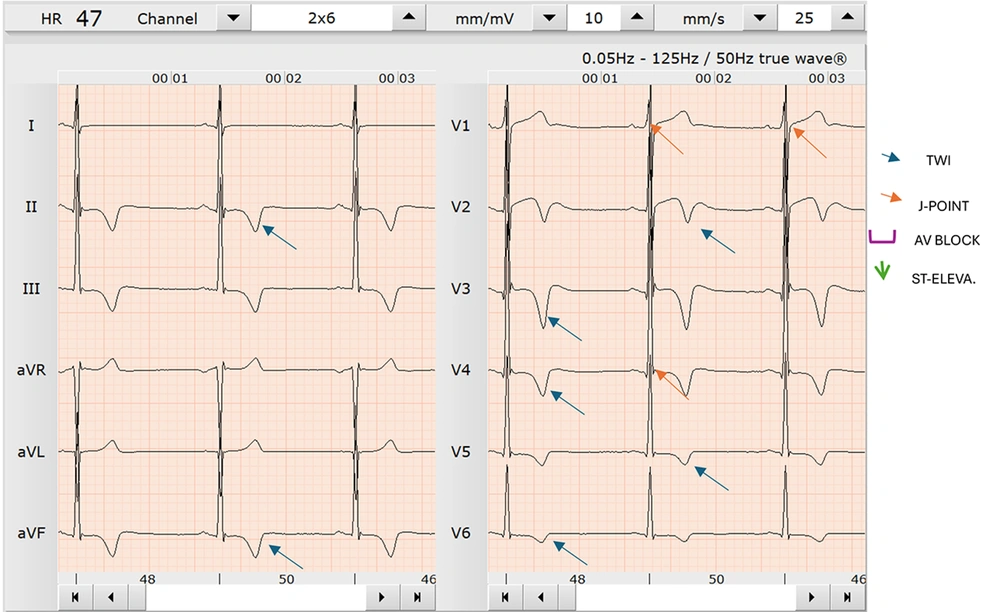

Athlete A is a 26-year-old South African male professional soccer player who presented for preseason medical screening. He was one of 105 players recruited for a research study examining the ECG profiles of black South African soccer players. During history taking, athlete A reported intermittent palpitations and throbbing abdominal pain during games. He noted that this abdominal pain was exacerbated by running and mostly experienced towards the end of a 90-minute soccer match, but he denied any history of collapsing on the field or experiencing chest pain. A 12-lead resting sport ECG test was performed on the athlete and analyzed using the European Society of Cardiology (ESC) international consensus standards for ECG interpretation in athletes. Common changes of T-wave inversion patterns for this population were observed, including inversions between leads V1-V6 and select limb leads (Figure 1). Specifically, athlete A presented with T-wave inversions in leads II, aVF, V2, V3, V4, V5, and V6 (Figure 1). These ECG changes were considered to be potentially pathological due to hypertrophic cardiomyopathy (HCM) with marked sinus bradycardia. Given these ECG abnormalities and the athlete’s reported symptoms, he was considered at high risk for SCA. According to the ESC international consensus standards for ECG interpretation in athletes, these changes are also classified as uncommon training-related changes. A stress ECG test was subsequently conducted to investigate the reported symptoms further (Figure 2). During the stress test, all the previously observed ECG changes were reversed, and no new T-wave inversions were noted. Although complex QRS changes were present, they were inconclusive and suggestive of a possible incomplete bundle branch block. The stress test was terminated due to the athlete's reproduction of the symptoms experienced during matches. These changes can also be attributed to exercise-induced vasodilation in skeletal muscle, which lowers systemic vascular resistance and increases cardiac output — resulting in reduced systolic blood pressure and more efficient blood delivery to the working muscles.

The athlete during a Bruce protocol stress test (load 8.0 km and gradient of 16%); this focuses on the precordial leads with no sign of any T-wave inversion. This is the same athlete displayed in Figure 1 [resting electrocardiogram (ECG)].